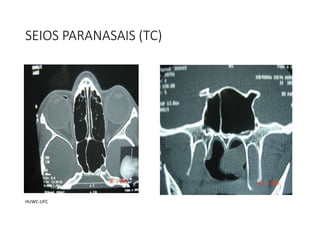

SEIOS PARANASAIS (TC)

HUWC-UFC